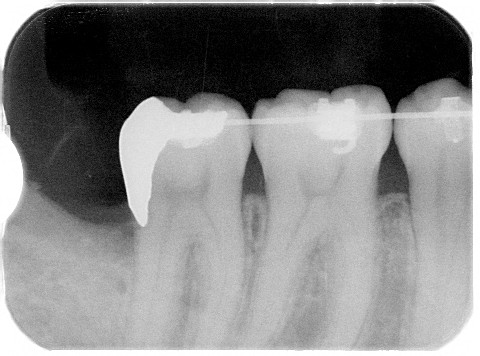

レントゲンを撮影すると親知らずの手前の歯が虫歯になっているではありませんか?

術後のインレーを入れた後のレントゲンです。